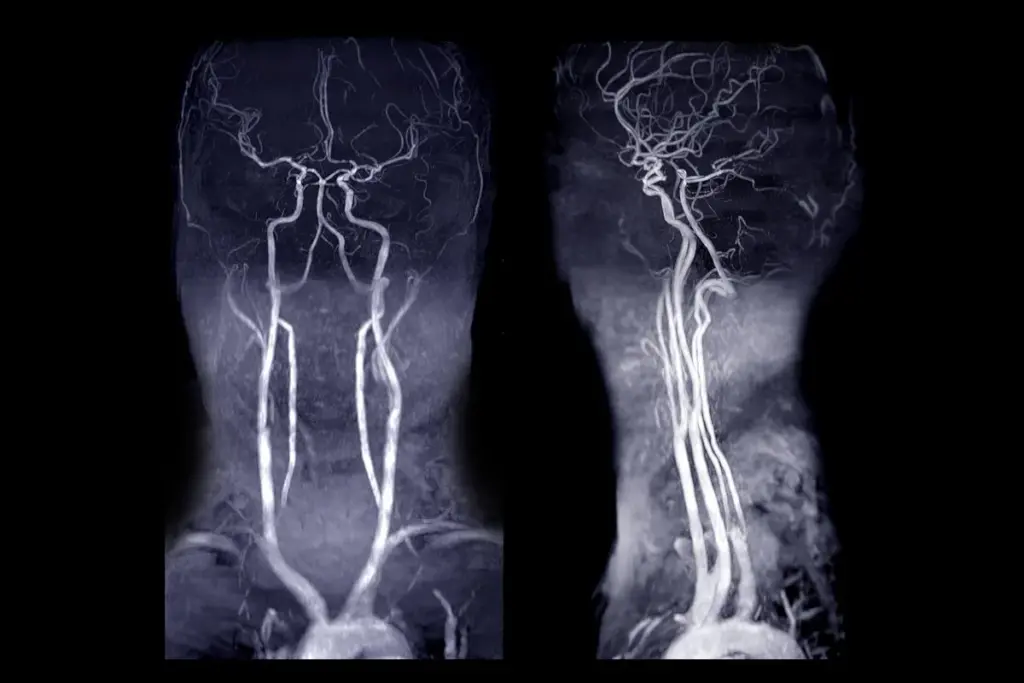

Magnetic Resonance Angiography (MRA)

MRI angiography, or MRA, is a non-invasive way to see blood vessels. It uses magnetic fields and radio waves. MRA is great for people who can’t have CT scans because of allergies or kidney issues. It shows blood flow and vessel details without using harmful radiation.

- MRA helps find problems like stenosis, aneurysms, and malformations.

- It’s good for checking blood vessels in the brain, neck, and limbs.

- Doctors can do MRA with or without contrast, depending on the case.